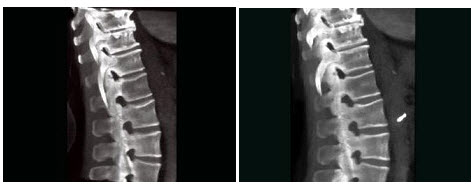

C.金